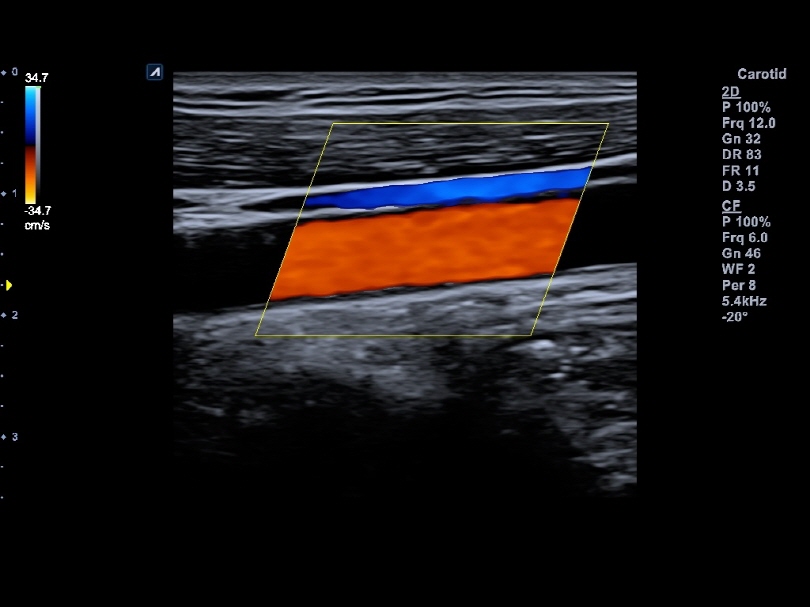

L8-17H

High density linear transducer(8-17MHz)

Application:

Breast, EM, MSK, Vascular, Small Parts

L3-12H

High density linear transducer (3-12MHz)

Application:

Breast, EM, MSK, Vascular, Small Parts

L3-12HWD

High density wide footprint linear transducer (3-12MHz)

Application:

Breast, EM, MSK, Vascular, Small Parts, Appendix

L3-12T

Linear transducer (3-12MHz)

Application:

Breast, EM, MSK, Vascular, Small Parts, Appendix